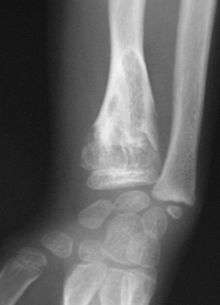

X-ray image showing enchondromas localized in the lower part of the radius of a 7-year-old girl with Ollier disease.

On radiographs, streaks of low density are seen projecting through the diaphyses into the epiphyses of the long bones, due to ectopic cartilage deposits. With age, the cartilage may calcify in the typical "snowflake" pattern.